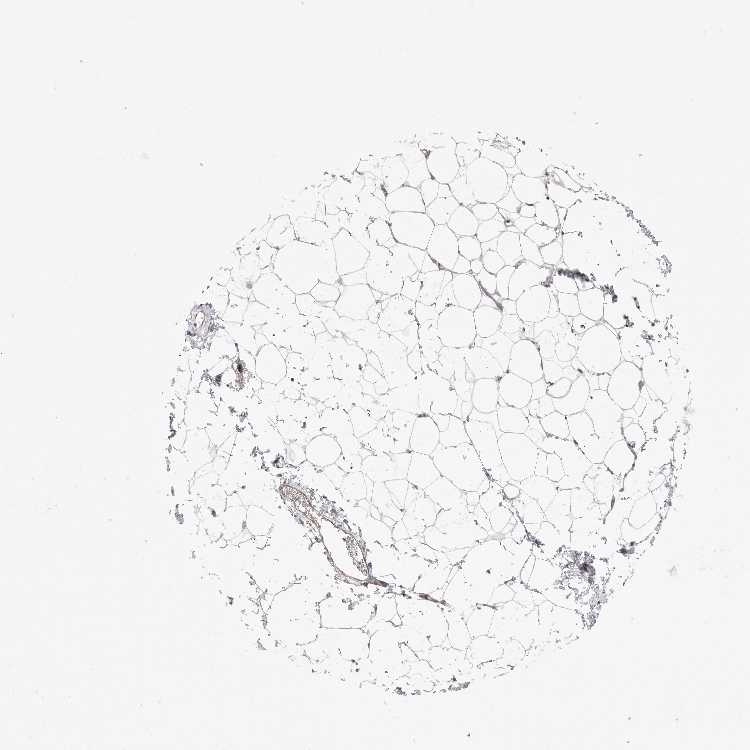

SOFT TISSUE 1 - Antibody stainingi

Antibody staining in the annotated cell types in the current human tissue is reported as not detected, low, medium, or high, based on conventional immunohistochemistry profiling in selected tissues. This score is based on the combination of the staining intensity and fraction of stained cells.

Each image is clickable and will lead to virtual microscopy that enables deeper exploration of all samples and also displays staining intensity scores, fraction scores and subcellular localization as well as patient and tissue information for each sample.

Antibody HPA027262

Chondrocytes Not detected

Fibroblasts Low

Peripheral nerve Medium